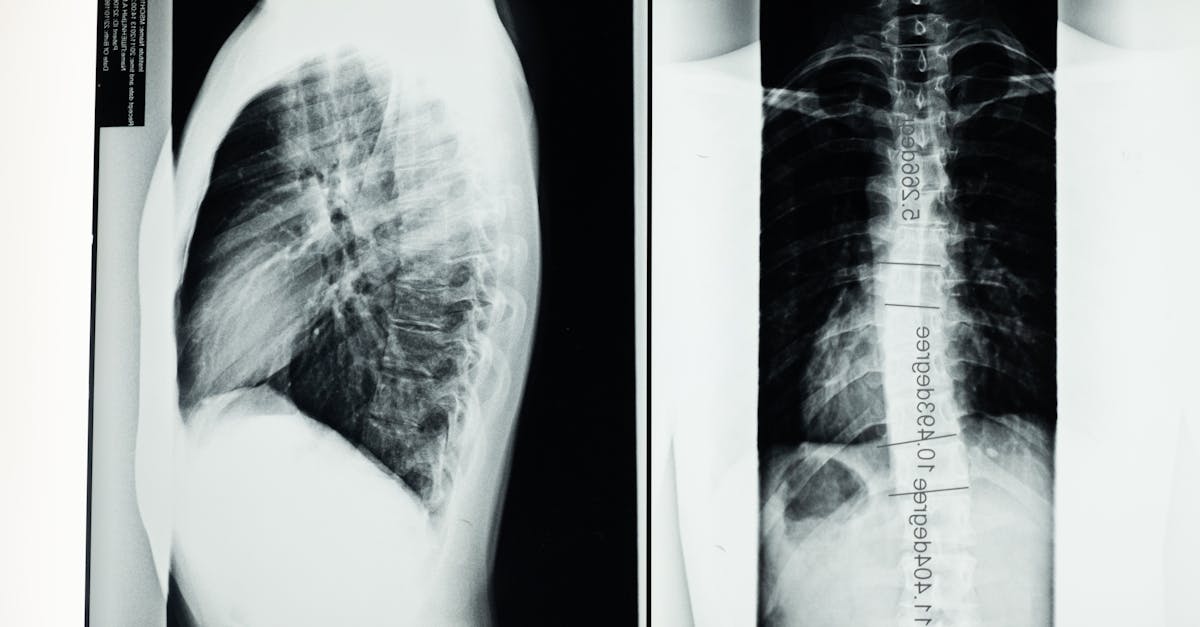

La décompression neurovertébrale repose sur une traction douce appliquée à la colonne vertébrale. Cette méthode crée un espace entre les vertèbres, ce qui réduit la pression sur les disques intervertébraux et les nerfs. Cette action améliore également la circulation sanguine au niveau des tissus affectés, ce qui aide à diminuer l’inflammation et favorise un processus de guérison naturel.

Cette méthode consiste à appliquer une traction douce sur la colonne vertébrale afin de créer un espace entre les vertèbres. En réduisant la pression exercée sur les disques intervertébraux et les nerfs, ce traitement permet d’améliorer la circulation sanguine et d’accélérer le processus de guérison. La décompression neurovertébrale est particulièrement efficace pour traiter des conditions telles que les hernies discales, les douleurs lombaires et cervicales, ainsi que d’autres troubles musculo-squelettiques.